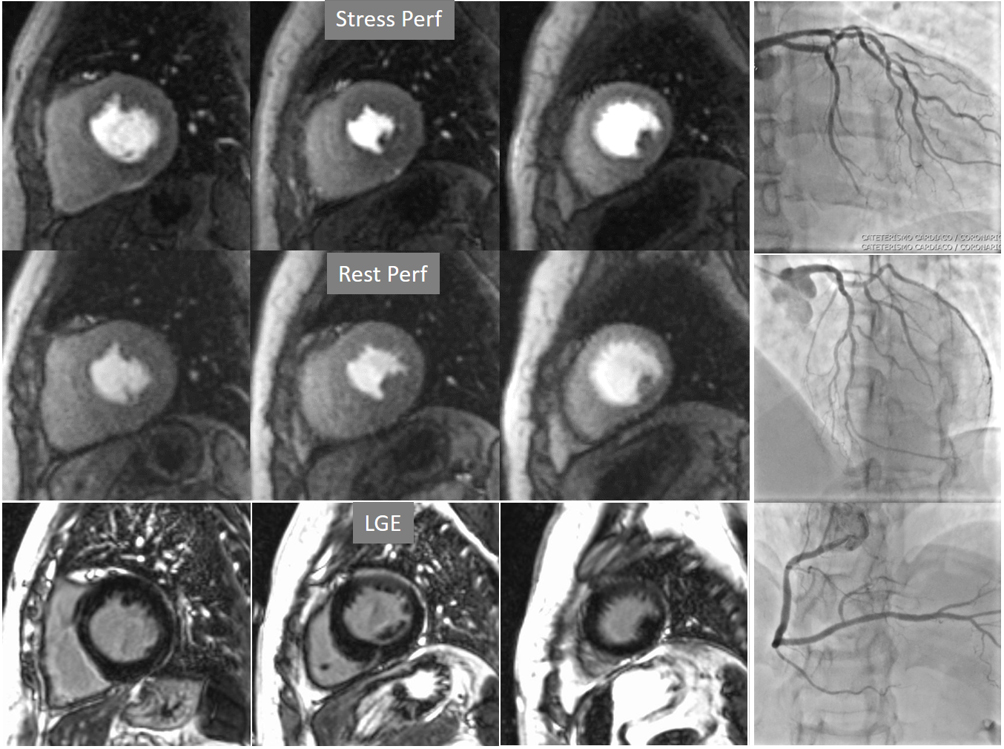

A not infrequent finding is a diffuse, annular, transient, subendocardial defect not present at rest (Fig. 9), which, in the absence of any recognizable obstructive lesion in an epicardial coronary artery, has been deemed to correspond to diffuse microvascular dysfunction (MVD) [41, 42]. CMR perfusion is sensitive to both the downstream effects of discrete epicardial stenoses and those due to disturbances of coronary microcirculation, and subendocardial hypoperfusion is on the pathophysiological basis of each one. For this reason, theoretically, a global, inducible subendocardial defect, could also be due to multivessel epicardial disease with balanced ischemia. In practice, however, this latter instance presents with extensive but heterogenous defects in terms of intensity, persistence and transmurality and, not rarely, also with perfusion defects at rest (Fig. 10A). Importantly, an accompanying induced contractile disfunction may be found in particularly impaired regions (Fig. 10B), a finding which is never seen in MVD.

Fig. 10.Multi-vessel perfusion defect. (A) Global stress hypoperfusion in a patient with multivessel CAD. Observe the non-uniformity of the defect, with different degrees of intensity and transmurality and, also, with the presence of a defect at rest (arrow), in the absence of LGE. (B) End-systolic frames from cine studies at the same level of the perfusion slices showing inducible antero-septal hypokinesia during stress (arrows).